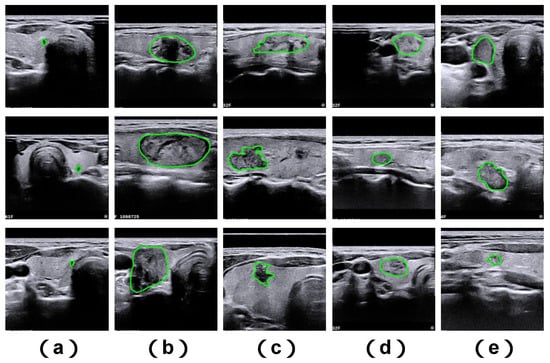

While current methodologies have enhanced performance in medical image analysis, segmenting medical images still poses notable challenges due to several key factors. First, the dimensions of clinically relevant objects within medical images may vary considerably (see Figure 1a,b). Second, ambiguous structural margins and complex geometries of segmentation targets often result in imprecise segmentation outcomes (see Figure 1c,d). Third, inadequate contrast levels make it difficult to differentiate between foreground anatomical targets and background image regions (see Figure 1e).

Figure 1. Illustrative examples of challenging thyroid nodule cases sourced from the TNUI-2021 ultrasound dataset. Shown here are: (a) diminutive nodules, (b) large-sized nodules, (c) nodules with irregular structural shapes, (d) nodules characterized by indistinct boundary edges, and (e) nodules associated with poor image contrast. The ground truth segmentation boundary is marked using a green annotation.